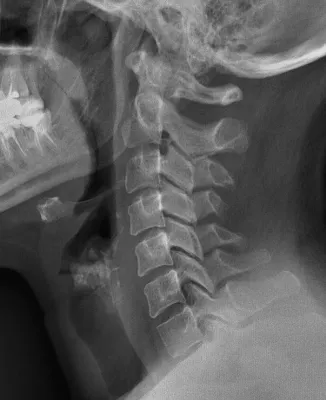

Faire une radiographie du rachis cervical

Radiographie du rachis cervical sont souvent demandée dans le bilan initial d'une douleur cervicale spontanée avec ou sans irradiation dans le bras, au suite à un traumatisme.Elles permettent de mettre en évidence les lésions traumatiques, dégénératives (arthrose) ainsi que les pincements discaux...